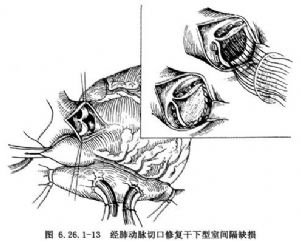

(3)修補缺損:這類缺損一般都比較大,且緊靠肺動脈瓣下方,缺損上緣即肺動脈瓣環,均應採用補片修補。剪裁與缺損形狀和大小相適應的補片,上緣應用帶墊片褥式縫合,分別縫於肺動脈瓣兜內的肺動脈瓣環上,於心室側出針,縫線分別穿過補片緣,將補片推下並結紮固定。其下方的肌肉緣與補片可用單純連續縫合,完全閉合室間隔缺損(圖6.26.1-13)。